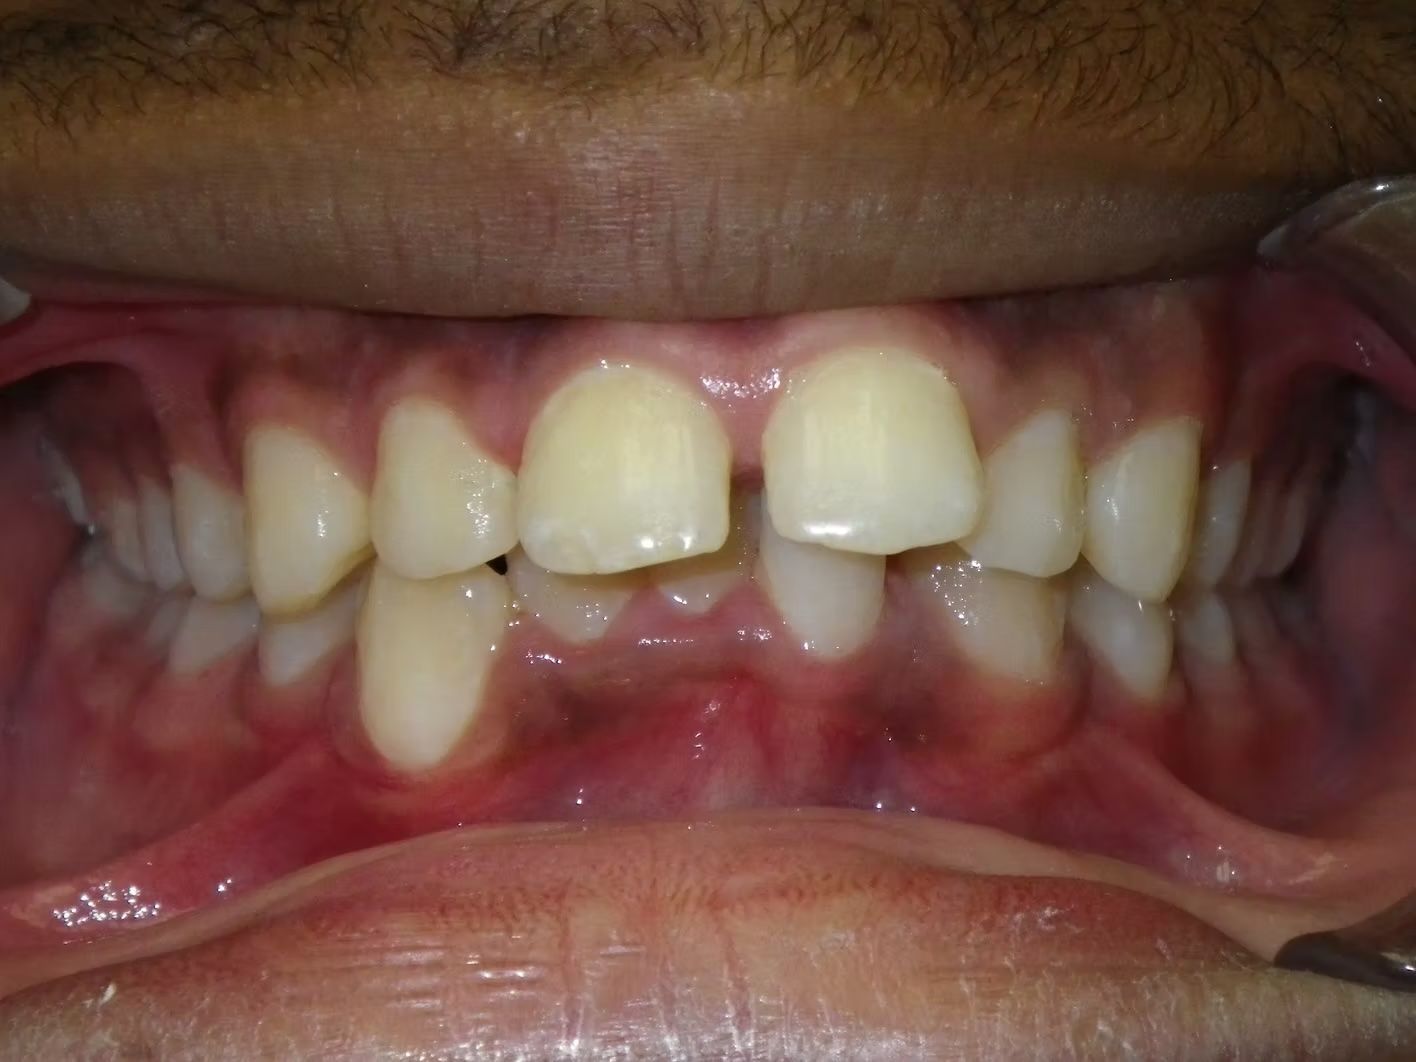

Imset

Imset came to see Dr. Bret because he felt like the upper and lower teeth were too crowded. The lower canines were in cross-bite with the upper teeth and there was significant crowding in the lower arch. He previously had 2 teeth pulled in the top and at the time none in the bottom. This made the top jaw smaller than the lower and the lower teeth didn't have room to fit inside the top teeth. We had 2 lower teeth extracted, and then aligned the upper and lower teeth to fit excellently together- no more crowding!